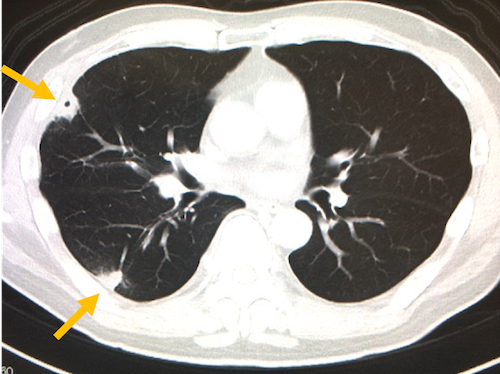

また左心系のIEではこのように全身の病変をきたしますが、右心系のIEでは肺野の胸膜直下付近にseptic emboliを形成し、空洞性病変を形成したりします。

これらのような病変を見たら(特に黄色ブドウ球菌による)感染性心内膜炎を疑います。

(引用:画像診断まとめ)